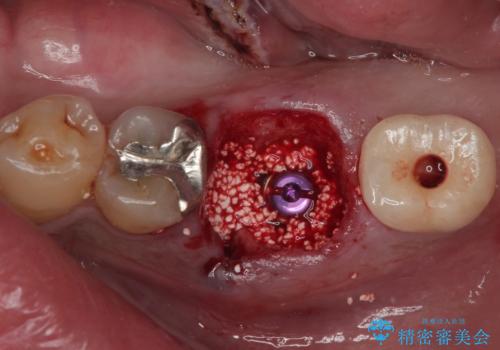

咬合力で破折した奥歯 抜歯即時インプラントで短期間治療

- 以前、咬合力の強さで歯の神経が失活してしまい、当院にて根管治療を行った患者様ですが、今度は咬合力の影響で歯根が破折してしまった患者様です。

歯根が破折してしまった歯は抜歯が必要となり、特に咬合力が強い方ですと、インプラント治療による治療がお勧めとなります。

従来のインプラント治療ですと、抜歯をしてからその部分の骨が回復するまで数か月待機し、その後インプラント埋入、生着を待って土台の頭出し手術、仮歯の装着となるため、咬合回復するまでに半年かそれ以上の期間が必要となってしまいます。

咬合力の影響で歯が壊れてしまう方の場合、長期間欠損が続くと、連鎖するように他の歯が壊されてしまうリスクがあるため、抜歯即時インプラントにより、治療期間の短縮を図ることとしました。

治療は順調に進み、わずか3ヶ月でセラミッククラウンを装着することができました。

他の歯への影響もなく、無事に治療を終えることができました。